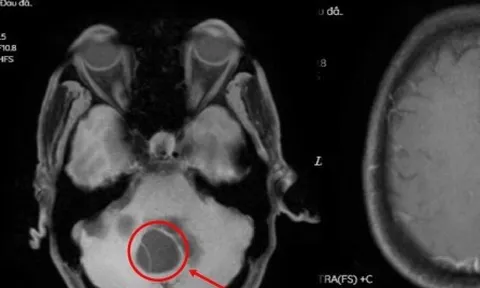

Sán làm tổ trong não do thói quen ăn tiết canh

Hai bệnh nhân nam nhập viện được chẩn đoán sán não do thói quen ăn tiết canh.